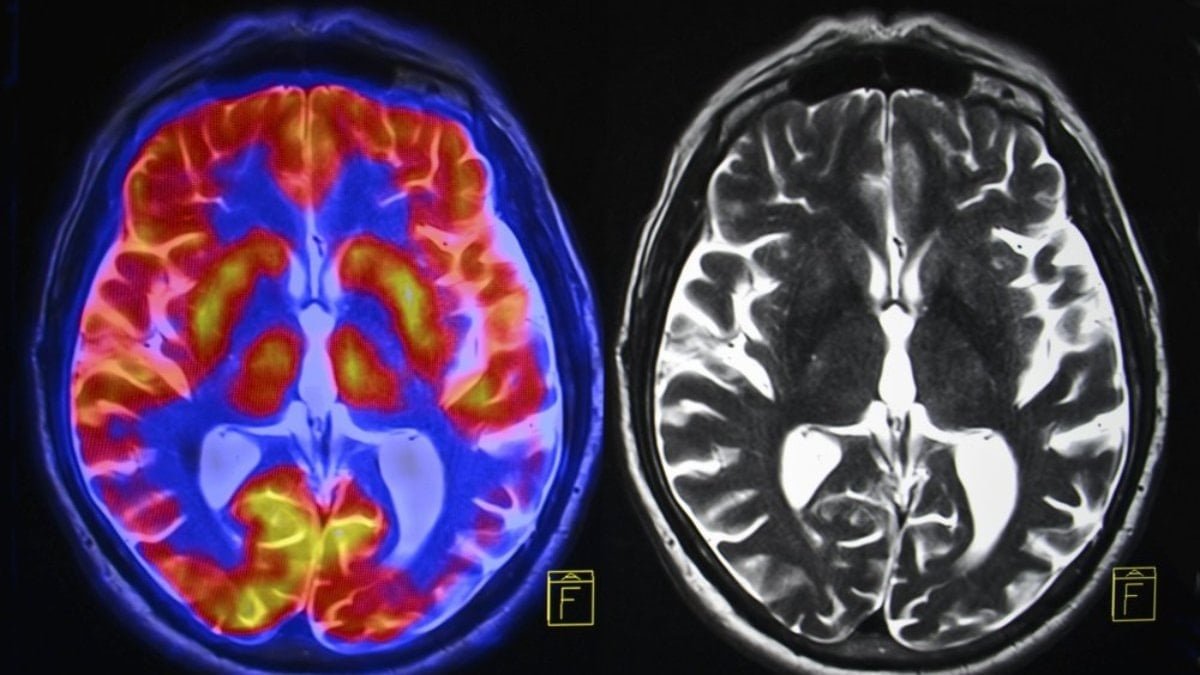

Beyin sağlığı için beslenmenin öneminin kaçırıldığına dikkat çeken Crawford, beyin sağlığı için yağlı balıkların daha sık tüketilmesi gerektiğinin de altını çizdi. Profesör Crawford, “Modern insan beyni, erken dönem atalarımızın beyinlerine göre yüzde 17 oranında daha küçük” dedi. Çocukların ve onların çocuklarının da geleceğinin risk altında olduğunu belirten Crawford, hamilelerin ve çocuk sahibi kadınların da çocukların emzirilmesi için omega-3 deposu balıkları tercih etmesi gerektiğini söyledi.